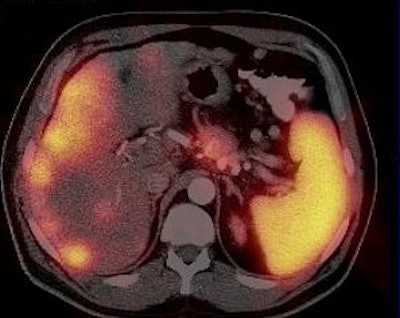

| A 52-year-old patient with pancreatic non-secretor neuroedocrine carcinoma low malignancy (NECLM; foregut; WHO type 2). SPECT and CT scans before start of 90Y DOTA TATE treatment, fusion images of standard CT after IV contrast enhancement and SRS using 99mTc HYNIC TATE. |